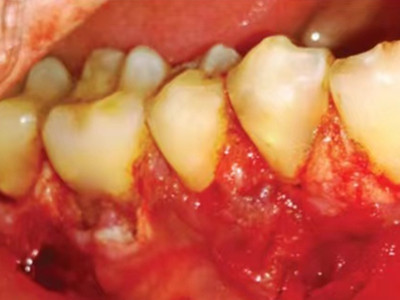

牙龈癌在口腔癌中仅次于舌癌而居第2位,组织学类型绝大多数为分化程度较高的鳞状细胞癌。牙龈癌好发于前磨牙区及磨牙区,下牙龈癌较上牙龈癌为多见,上下之比为2:1。牙龈癌发病年龄多为40-60岁,男性多于女性。

牙龈癌多源于牙间乳头及龈缘区,溃疡呈表浅、淡红,以后可出现增生。由于黏骨膜与牙槽突附着甚紧,较易早期侵犯牙槽突骨膜及骨质,进而出现牙松动,并可发生脱落。X线片可出现恶性肿瘤的破坏特征虫蚀状不规则吸收。

牙龈癌常发生继发感染,肿瘤伴以坏死组织,触之易出血。体积过大时可出现面部肿胀,浸润皮肤。